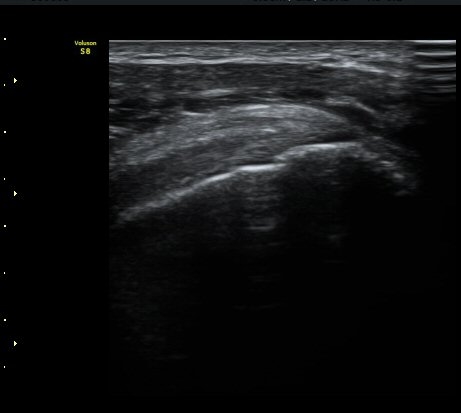

ÃÊÀ½ÆÄ °Ë»ç

ÀÌµÎ¹Ú±Ù°Ç È¾´Ü¸é°Ë»ç¿¡¼­ ƯÀÌ ¼Ò°ßÀ» º¸ÀÌÁö ¾ÊÀ½(»çÁø 1, 2).

±Ø»ó°Ç Á¾´Ü¸é°Ë»ç¿¡¼­ ±Ø»ó°Ç ÆÄ¿­Àº º¸ÀÌÁö ¾ÊÀ¸³ª »ó¿Ï°ñ ´ë°áÀý°ú °ñµÎ ÀÌÇàºÎÀ§¿¡¼­

ÇÇÁú°ñ ¿¬°á ¼Ò½Ç°ú ¹Ì¼¼ÇÑ °ñÆíÀÌ °üÂûµÊ(»çÁø 3, 4, 5).

±Ø»ó°Ç Ⱦ´Ü¸é°Ë»ç¿¡¼­ ±Ø»ó°Ç ±ÙÀ§ºÎ¿¡¼­´Â ƯÀÌ ¼Ò°ßÀ» º¸ÀÌÁö ¾ÊÀ¸³ª ±Ø»ó°Ç ¿øÀ§ºÎ¿¡¼­

ÇÇÁú°ñ ¿¬°á ¼Ò½Ç°ú ¹Ì¼¼ÇÑ °ñÆíÀÌ °üÂûµÊ(»çÁø 6, 7).